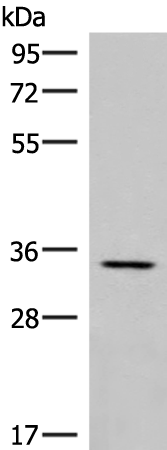

分类: 科研抗体货号: P05754别名: 2410091M23Rik应用: WB,IHC反应种属: Human